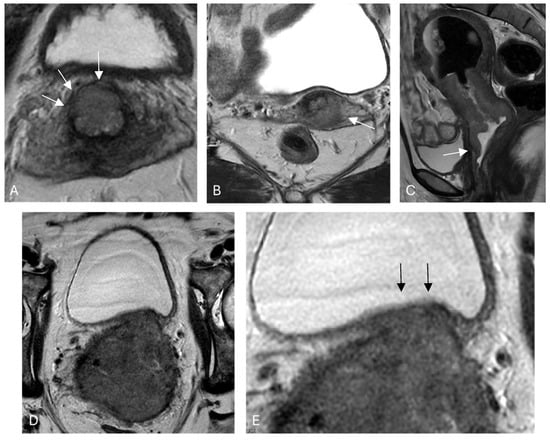

3.1. Stromal Invasion

3.2. Parametrial Invasion

3.3. Vaginal Involvement

3.4. Pelvic Side Wall

3.5. Lymph Node Metastasis

3.6. Bladder and Rectal Involvement